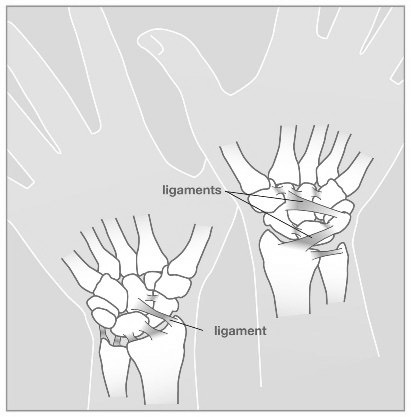

These are some of the main ligaments in the wrist. These ligaments hold the small bones of the wrist together to themselves and to the end of the radius and ulna. These ligaments serve a very important function for the wrist. When these ligaments are injured they can cause significan dysfunction to the wrist.